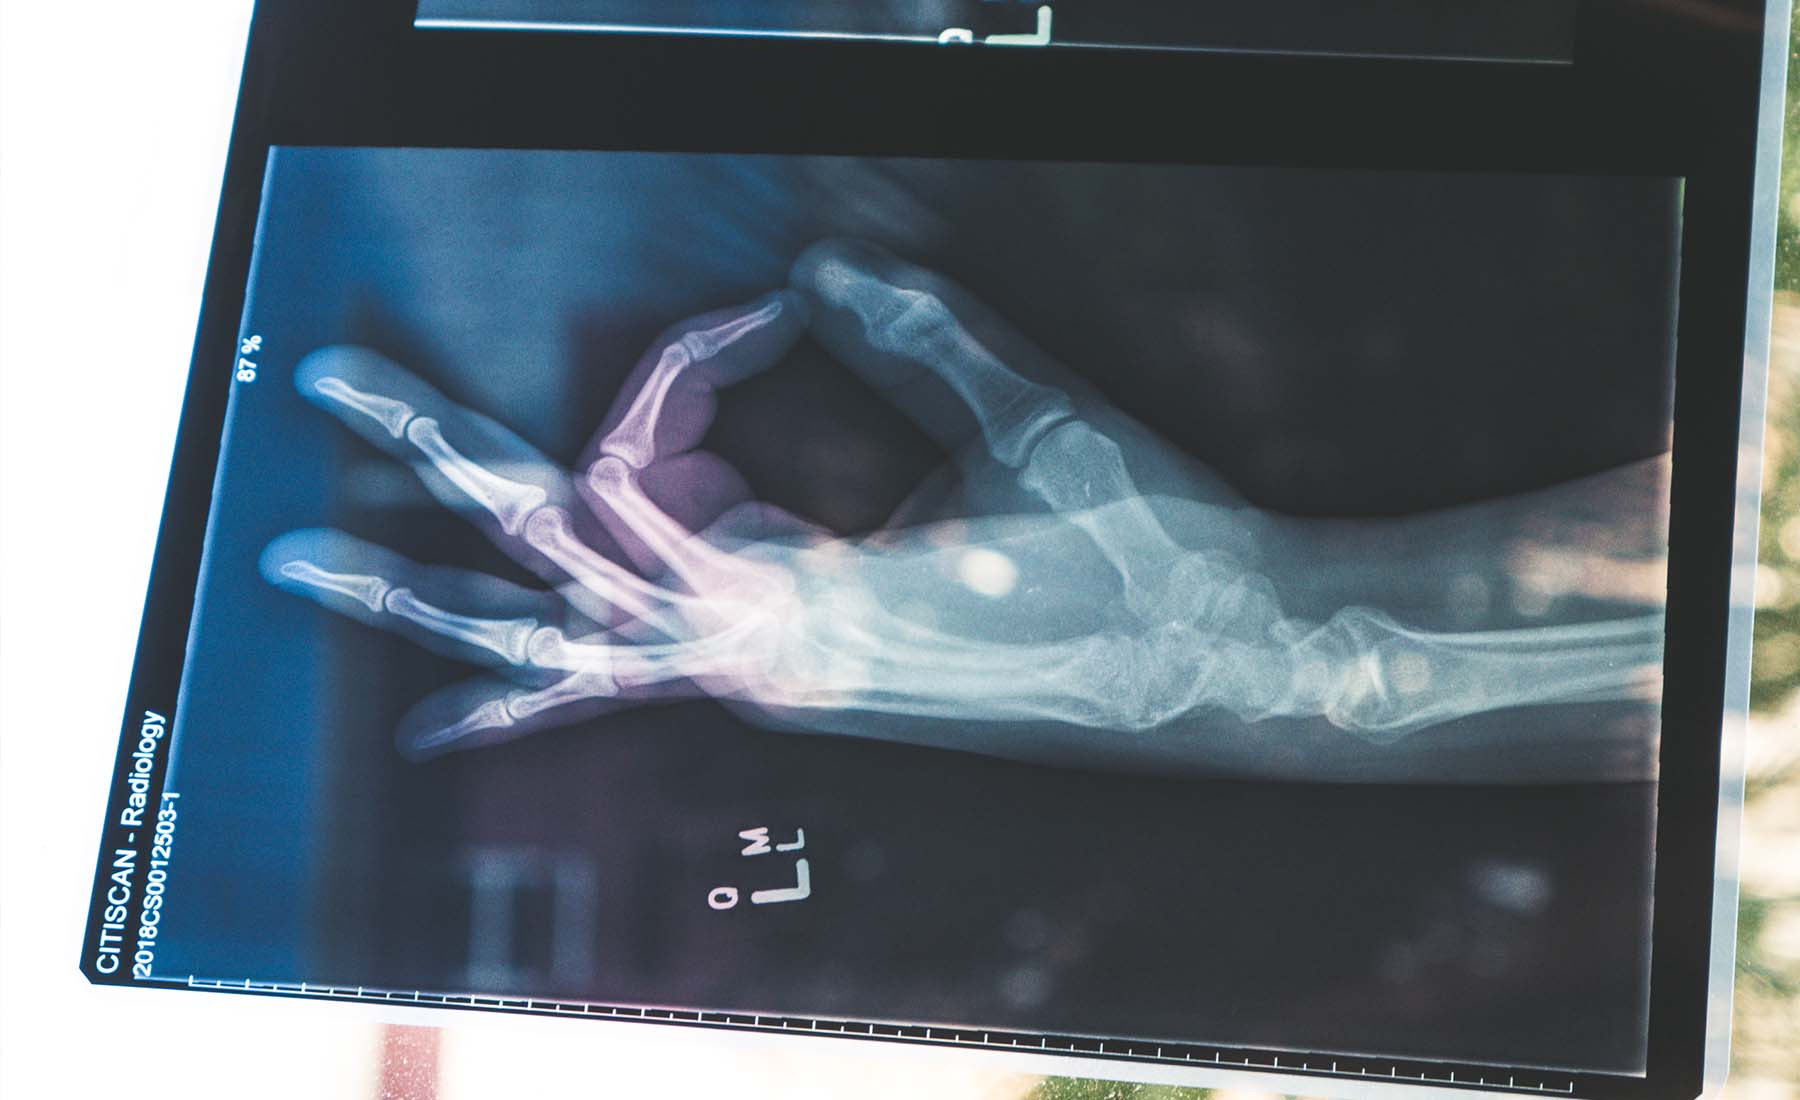

10 aliments qui donnent des os solides

De nombreux nutriments sont impliqués dans le maintien des os en bonne santé. Le calcium et la vitamine D sont deux des plus importants.

Le calcium est un minéral essentiel au bon fonctionnement de votre corps et est stocké dans vos os. Votre corps a besoin de vitamine D pour absorber le calcium. Un apport insuffisant en calcium dans votre alimentation peut entraîner la fragilité et la fragilité des os, qui sont plus sujets aux fractures et aux maladies.

La vitamine K, la vitamine C, le magnésium et le phosphore sont d'autres nutriments importants pour la santé des os.

En vieillissant, votre corps continuera à avoir besoin de calcium, de vitamine D et d'autres nutriments pour que vos os restent solides et denses. L'apport d'une quantité suffisante de nutriments pour soutenir les os dans votre alimentation est peut-être la chose la plus importante que vous puissiez faire pour les garder forts et en bonne santé.